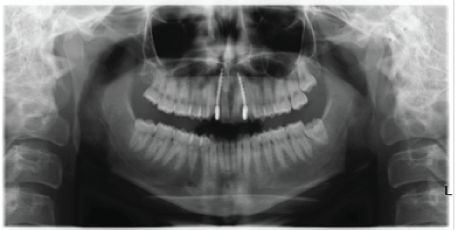

Figure 1: The case of the young male patient suffering from bilateral agenesis. The lack of space between central incisors and canine can be observed.

This report is about a 13.y.o. male patient, Caucasian, suffering from agenesis of both lateral incisors in bilateral class one molar (2.1 1.2) in good health status. He showed a deep bite, resulting in a remarkable reduction of transverse diameters in the central group.

The above pictures prove, therefore, how the orthodontic Invisalign® treatment ensured to achieve more space. In this very case, the therapy lasted from May 2011 until April 2014, using overall 90 aligners gaining a total of 4,9 mm as space for the 1.2 and 4.8 mm for the 2.2.

The edentulous condition is characterized by little available space, in addition to remarkable bone atrophy. In order to restore the missing tooth, the procedure, previously described, was performed by employing, eventually, noble-metal alloy, and ceramic (Ivoclar Vivadent InLine®) crowns (Figures 1-8).